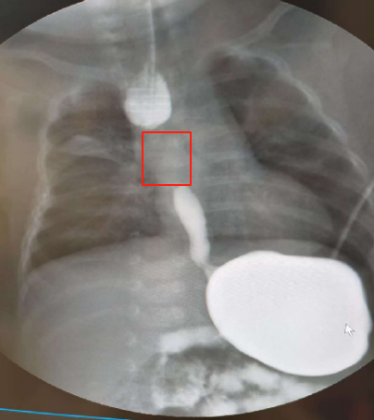

小扎西的食管“断开”了4厘米。受访者供图

6月2日,影像检查显示,小扎西的食管终于“养”好了。

“他上下食管的重叠段约有1厘米,体重也长到了12斤,基本达到了做食管闭锁吻合术的条件。”赵勇说。